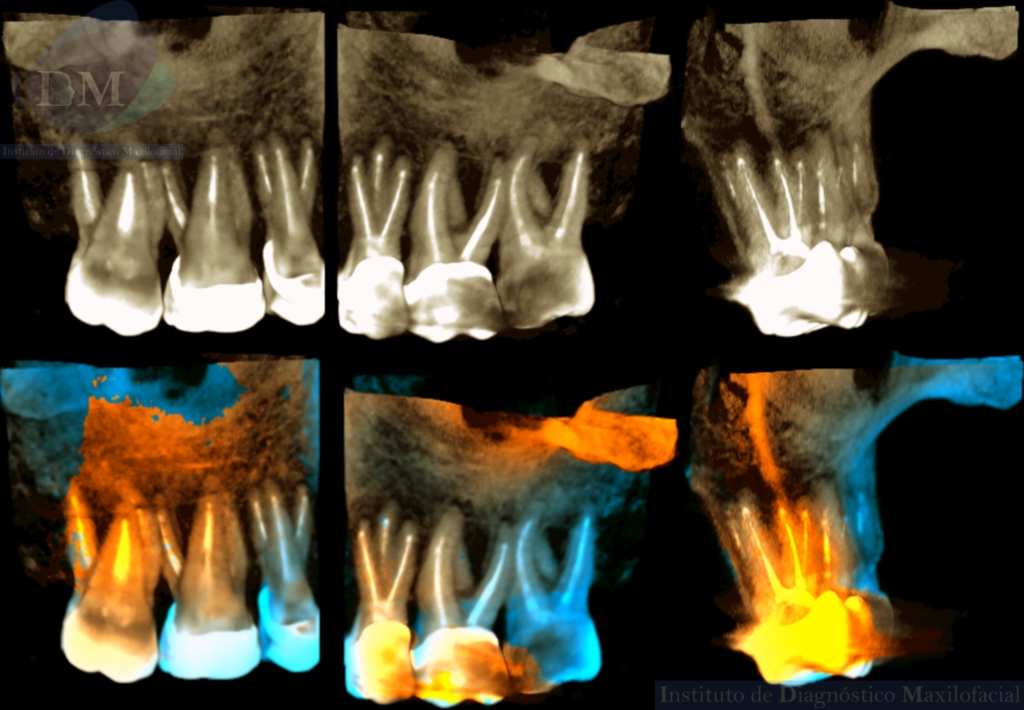

A la evaluación de la radiografía panorámica se evidencia múltiples piezas con tratamientos de conductos y múltiples restauraciones. Presentando un implante con prótesis sobre implante en zona de la pieza 36.

Así mismo en la tomografía volumétrica de haz cónico localizada se evidencia como hallazgo imagenológico, la presencia de tres segmentos radiculares con material de obturación de conductos en la pieza 25. Siendo dos raíces vestibulares (mesial y distal) y una raíz palatina.

RECONSTRUCCIÓN 3D